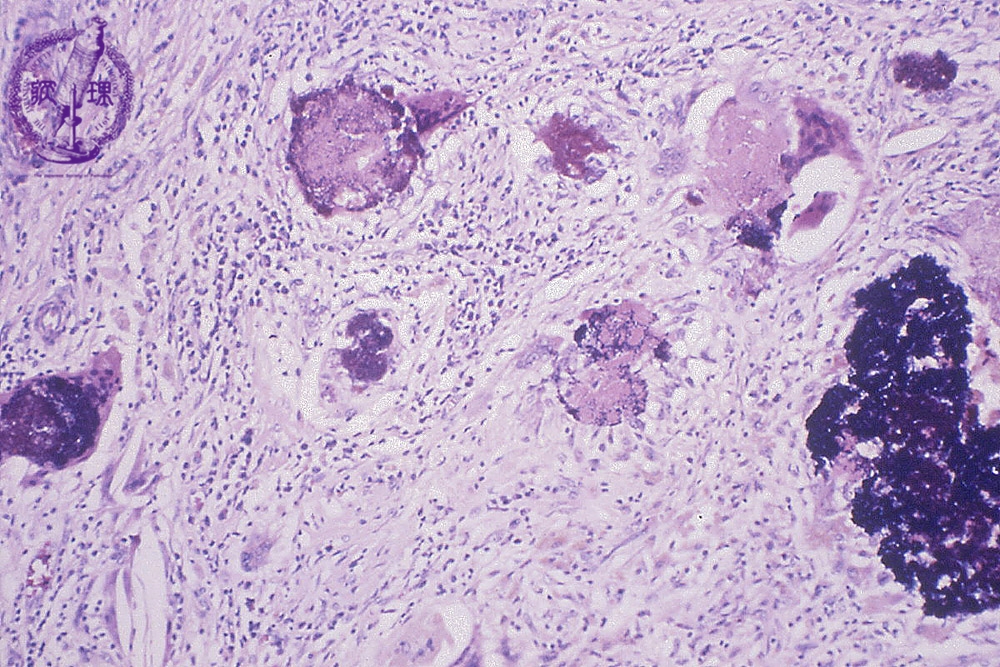

- (3)Sperm granuloma

Histology (HE stain, intermediate power): Accompanied by chronic inflammatory cells infiltration, granulomatous reaction with foreign body giant cells (black arrow) is identified. This granulomatous reaction dues to the extravasation of spermatozoa outside the tubules in epididymis. It formes about 1 cm nodule. Trauma, epididymitis or vasoligation can induce this pathology.